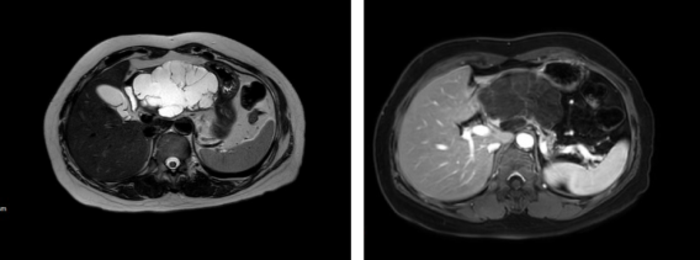

粘液性囊腺瘤(MCN),女性多见,影像特点:单房多见,囊壁可能有钙化(蛋壳样),体尾部多见;病理特点:MCN肿瘤多为囊性,囊壁内衬单层粘液柱状上皮,上皮下方为卵巢样间质。潜在恶性,建议手术。(下图为一例典型的MCN的CT表现,囊壁会有轻度强化)

浆液性囊腺瘤(SCN),多发微囊,中央可有瘢痕,CT增强后表现为轻度强化,中心钙化,“石榴”,这个良性肿瘤,一般不需要手术,只有在出现压迫症状(腹痛,呕吐,黄疸等)或不能排除恶性肿瘤时候可考虑手术。病理特点:SCN肿瘤由大小不一的囊腔构成,内衬透明立方上皮,上皮下方为毛细血管网。(下图为一例典型的SCN的MRI表现)